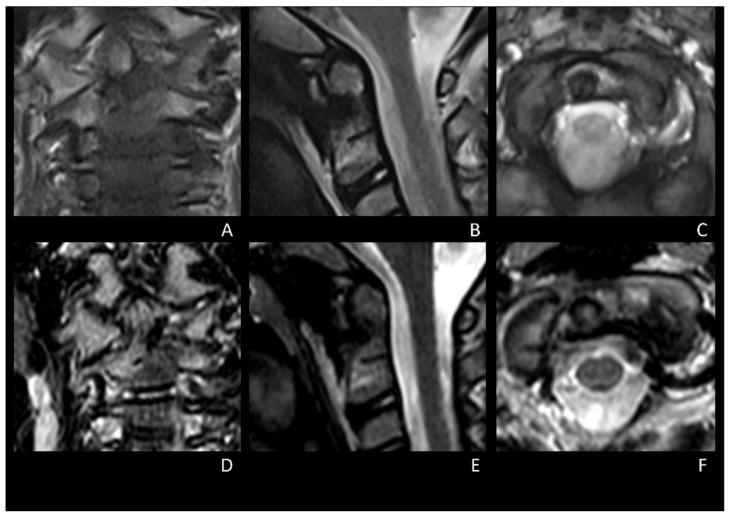

Osteoid osteoma (OO) is a primary benign tumor that accounts for up to 3% of all bone tumors. The cervical spine is less affected by OOs, and very few cases of C2 OOs have been reported in the literature, both in adults and children. Surgery may be required in case of functional torticollis, stiffness, and reduced range of motion (ROM) due to cervical OOs refractory to medical therapy. Several posterior and anterior surgical techniques have been described to remove C2 OOs. In particular, anterior approaches to the cervical spine represent the most used surgical route for treating C2 OOs. We describe the first case of OO of the odontoid process removed through a transnasal endoscopic approach with the aid of neuronavigation in a 6-year-old child. No intraoperative complications occurred, and the post-operative course was uneventful. The patient had immediate relief of neck pain and remained pain-free throughout the follow-up period, with complete functional recovery of the neck range of motion (ROM). In this case, based on the favorable anatomy, the transnasal endoscopic approach represented a valuable strategy for the complete removal of an anterior C2 OO without the need for further vertebral fixation since the preservation of ligaments and paravertebral soft tissue.

骨样骨瘤(OO)是一种原发性良性肿瘤,占所有骨肿瘤的比例高达3%。颈椎受骨样骨瘤影响较少,无论是成人还是儿童,文献中报道的C2骨样骨瘤病例都非常少。对于因药物治疗无效的颈椎骨样骨瘤导致的功能性斜颈、僵硬和活动范围(ROM)减小的情况,可能需要进行手术。已经描述了几种后路和前路手术技术来切除C2骨样骨瘤。特别是,颈椎前路手术是治疗C2骨样骨瘤最常用的手术途径。我们描述了第一例在一名6岁儿童中,借助神经导航通过经鼻内镜手术切除齿状突骨样骨瘤的病例。术中未发生并发症,术后过程顺利。患者颈部疼痛立即缓解,在整个随访期间均无疼痛,颈部活动范围(ROM)完全恢复功能。在该病例中,基于有利的解剖结构,经鼻内镜手术是一种有价值的策略,可在保留韧带和椎旁软组织的情况下,无需进一步椎体固定即可完全切除C2前部骨样骨瘤。